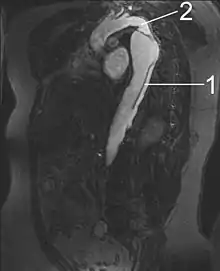

MRI of an aortic dissection

1. Aorta descendens with dissection

2. Aorta isthmus

Magnetic resonance imaging (MRI) is also used for the detection and assessment of aortic dissection, with a sensitivity of 98% and a specificity of 98%. An MRI examination of the aorta produces a three-dimensional reconstruction of the aorta, allowing the physician to determine the location of the intimal tear and the involvement of branch vessels, and to locate any secondary tears. It is a noninvasive test, does not require the use of iodinated contrast material, and can detect and quantitate the degree of aortic insufficiency.

The disadvantage of the MRI scan in the face of aortic dissection is that it may be available only in larger hospitals, and the scan is relatively time-consuming, which could be dangerous in people who are already very unwell. Due to the high-intensity magnetic fields used during MRI, it cannot be used on individuals with metallic implants. In addition, some individuals experience claustrophobia while surrounded by the MRI magnet.